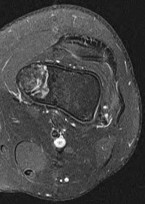

Question 6

A 22-year-old soccer player sustains a twisting injury to the knee resulting in a rapid effusion. MRI demonstrates a complete midsubstance rupture of the anterior cruciate ligament (ACL).

Which of the following concomitant meniscal injuries is statistically most commonly associated with an acute ACL rupture?

Explanation

In the setting of an acute ACL tear, tears of the lateral meniscus (particularly the posterior horn) are the most common concomitant meniscal injury, seen in roughly 50-70% of acute cases. Conversely, in the chronic ACL-deficient knee, medial meniscus tears become much more common due to the long-term altered kinematics and repeated anterior translation of the tibia, which puts the posterior horn of the medial meniscus under chronic shear stress.